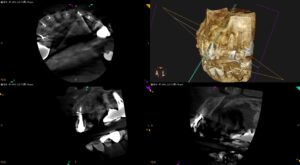

紹介患者さんの治療。 主訴は、 前歯にできものが出来て歯が痛い… である。 ⭐︎この後、検査/外科動画が出てきます。不快感を感じる方は視聴をSkipしてください。 歯内療法学的検査(2025.2.6) #24 Cold+ … 続きを読む 前歯にできものが出来て歯が痛い…〜#8,9 MicroSurgery